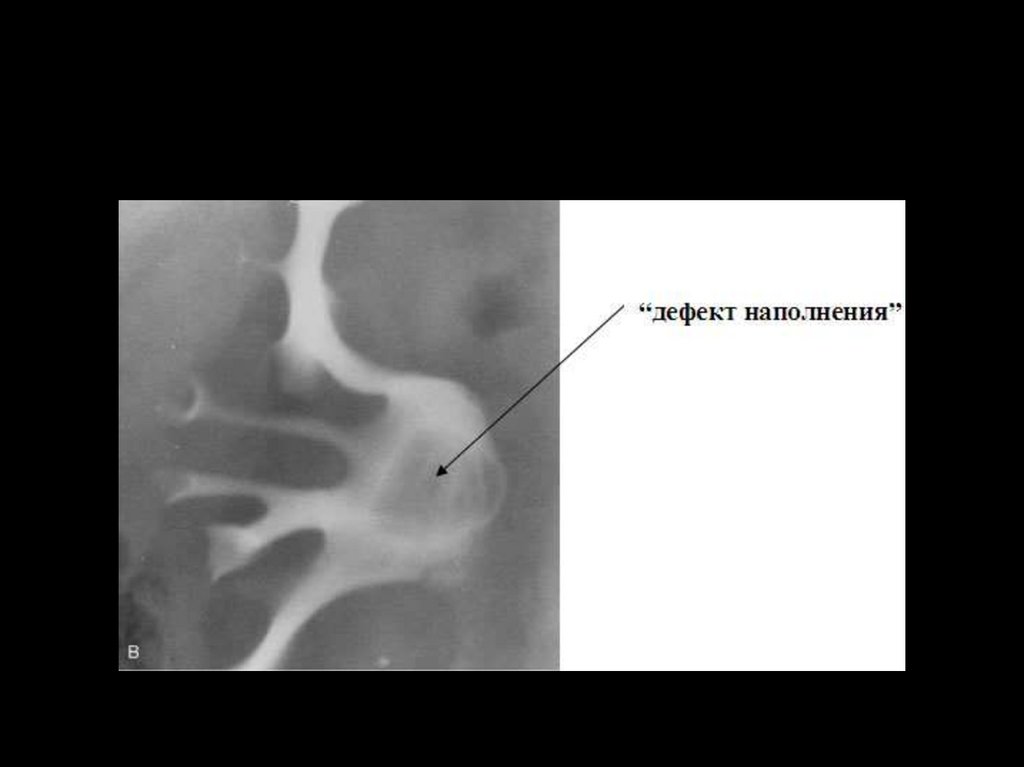

При

рентгенонегативном

камне

на

фоне

рентгеноконтрастного вещества виден "дефект наполнения",

соответствующий локализации конкремента .